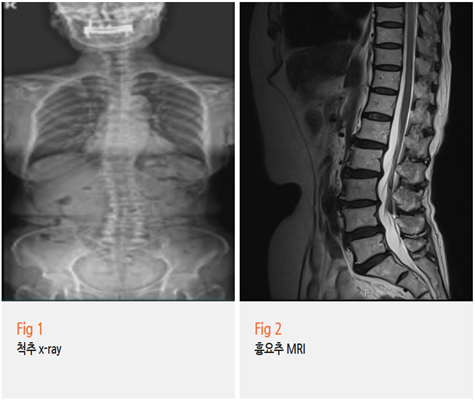

그래서 저는 바로 정밀검사를 시행했습니다.

✅ MRI로 척추 상태 확인

그림3.png 촬영 일시: 2025.04.11

✔️요추 퇴행성 디스크

✔️요추 4-5번 전방전위증

✔️경추 6-7번 디스크 탈출증

✔️척추 측만증

✔️근감소증

그리고 이 모든 것들이 복합적으로 작용해서

자율신경 기능 장애까지 유발한 상태였어요.